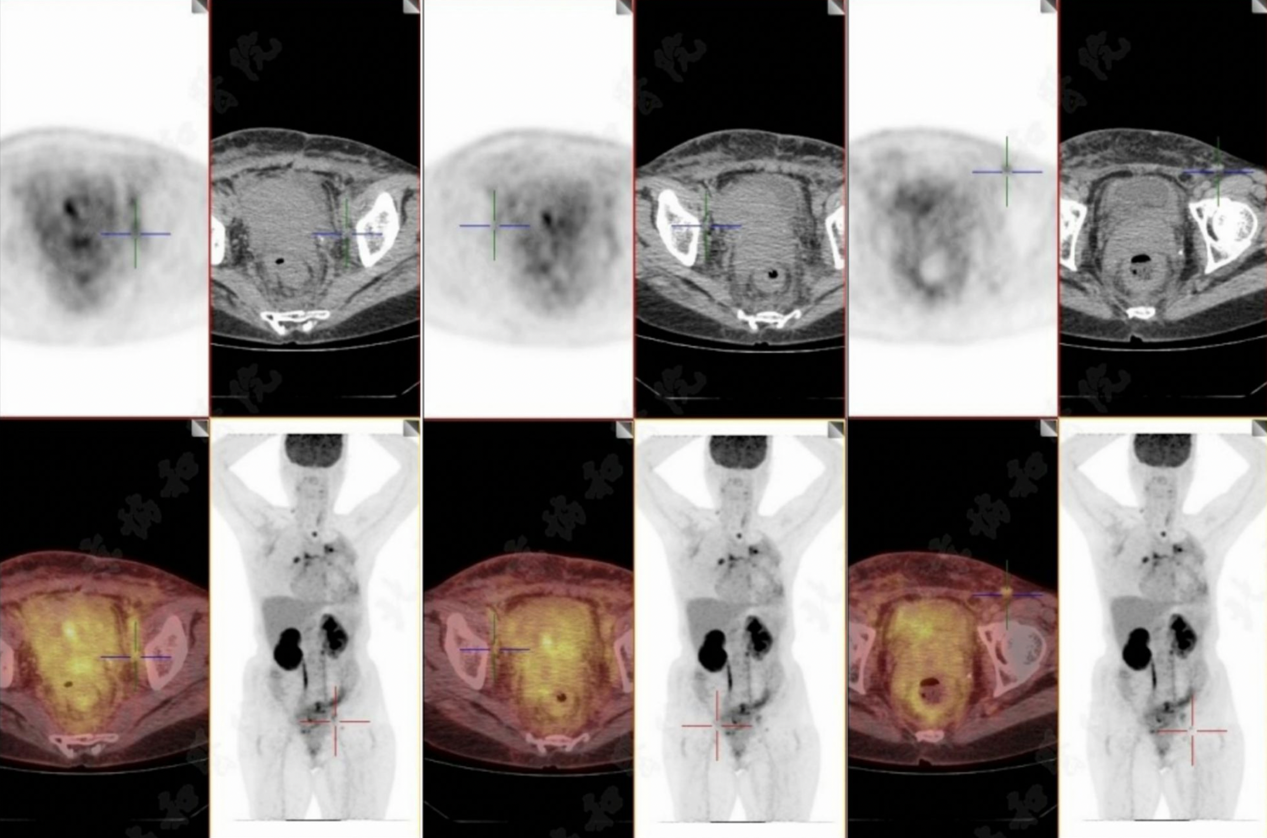

目前患者存在广泛全身转移,累及骨、淋巴结、胸膜、心包和直肠(图3)。已置入肠道支架以缓解梗阻。